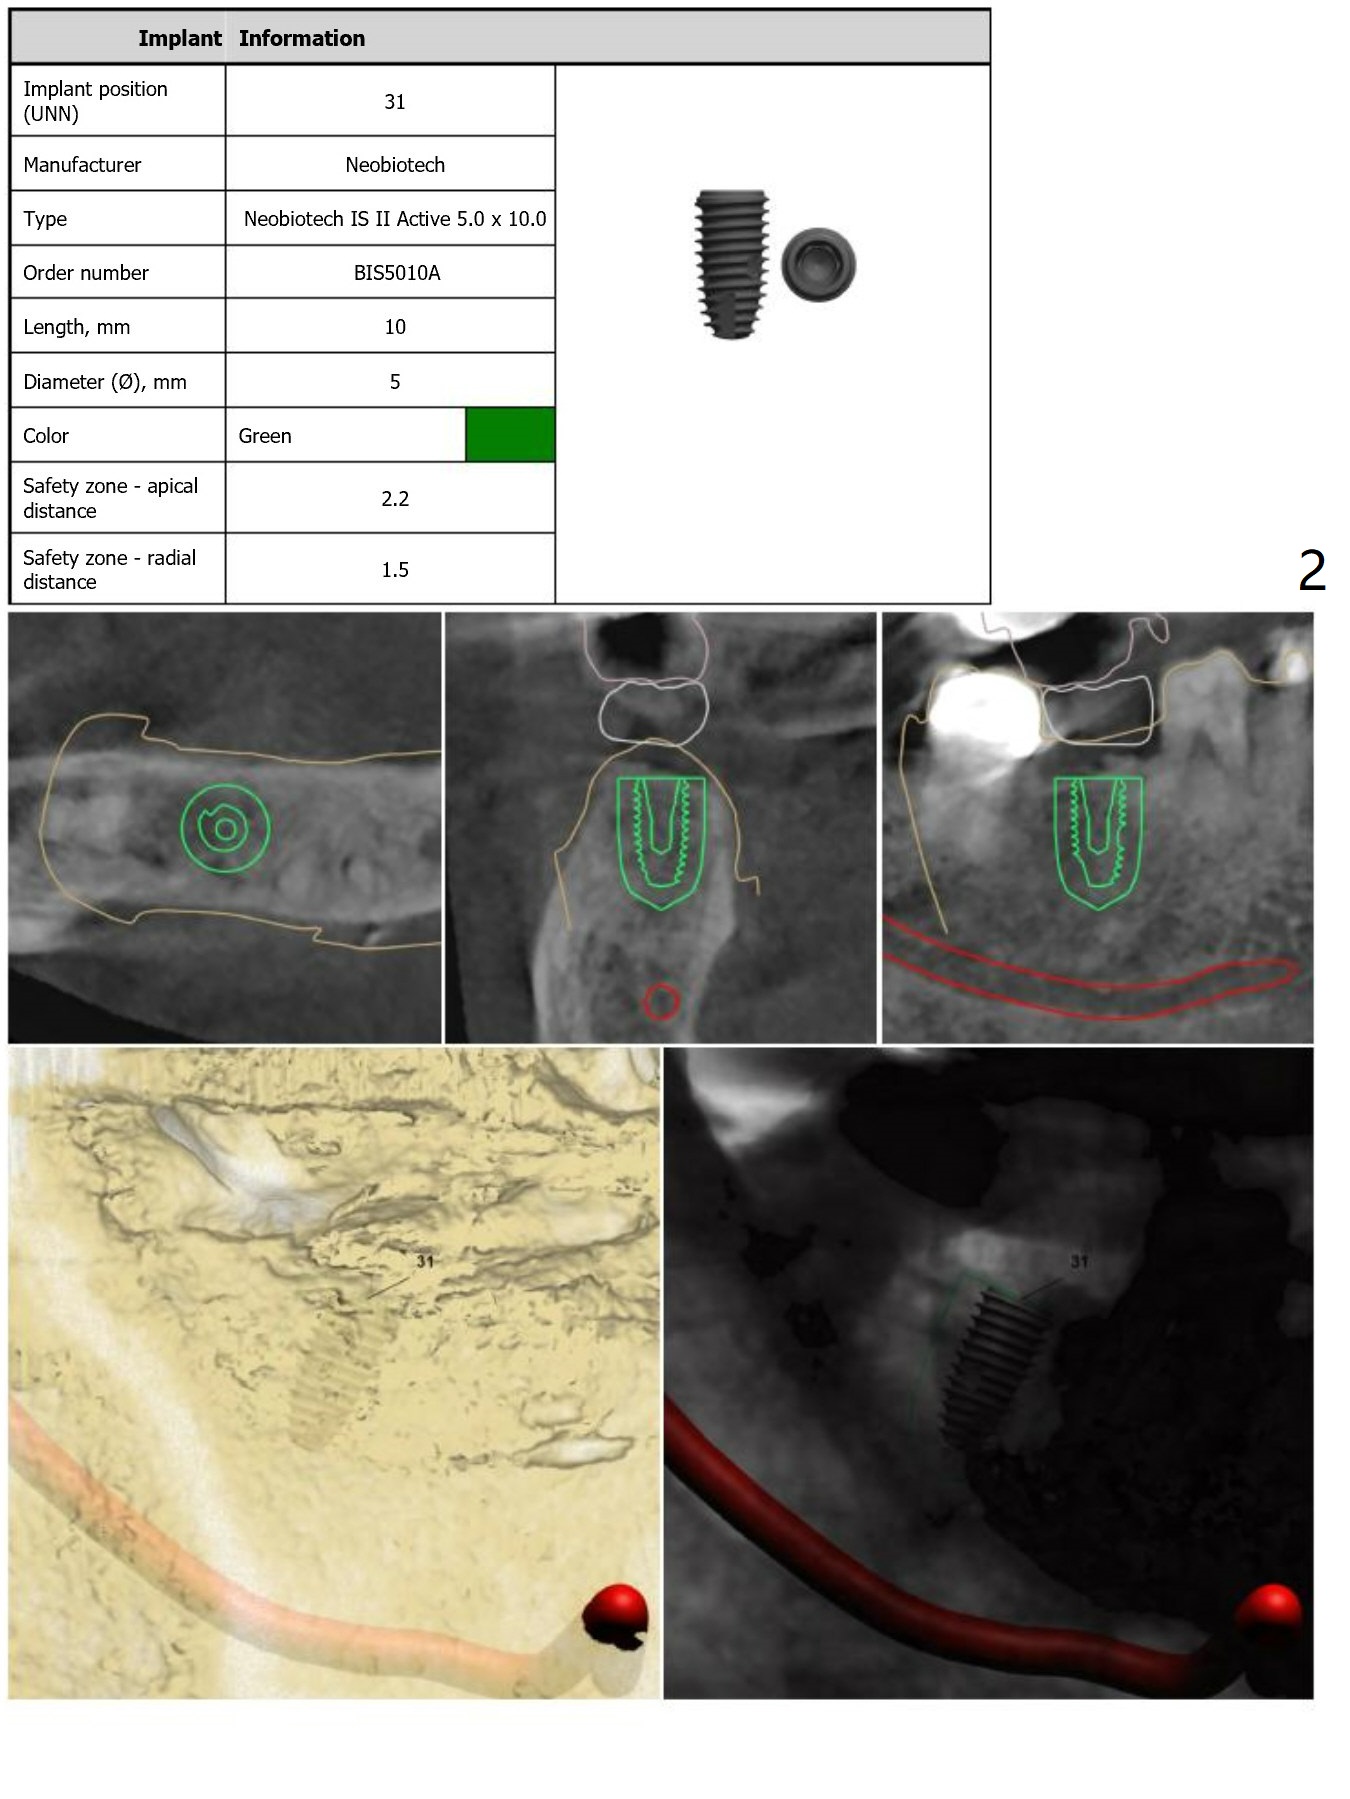

Crestal Level

The distal crest is lower than the mesial one. The 5x10 mm implant is level with the distal crest (Fig.2).